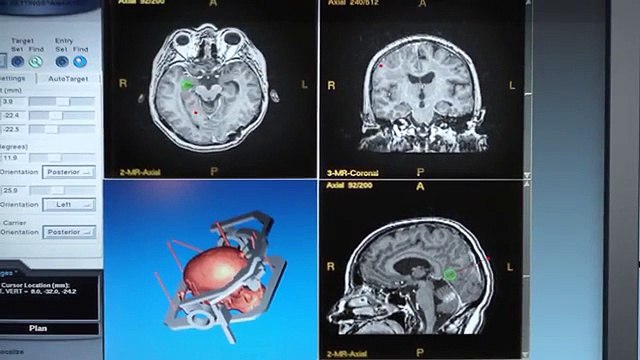

Узнайте больше о стоимости Опухоль головного мозга хирургии Индии, лечение опухолей головного мозга, причины, симптомы, виды, хирургическое вмешательство и лечение лучших врачей фортис больницы, Макс больницы Индии и т.д. Получите доступное недорогое медицинское лечение в Индии. Посещение: russian.indiahealthhelp.com/ Или позвонить по телефону : +91-9999950957